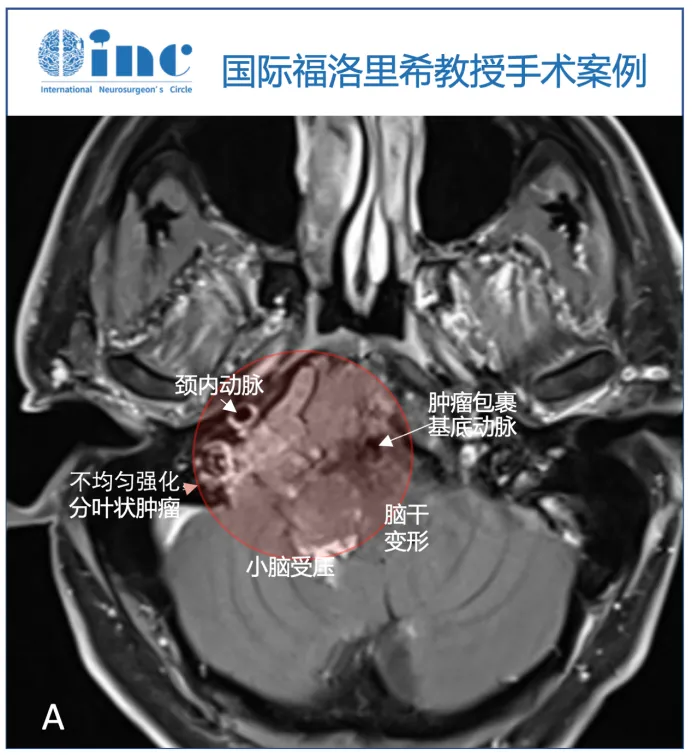

33岁男性出现发声困难(声音嘶哑),伴进行性右侧半舌麻痹及左上臂无力。影像学显示颅颈交界处巨大轴外病变,符合脊索瘤特征:T1WI呈等信号,T2WI呈高信号,强化不均匀。肿瘤以右侧岩斜坡软骨联合为中心,向下延伸至颅颈交界处,硬膜内延伸至Luschka孔,压迫脑干。增强扫描显示肿瘤压迫的小脑最后部分亦强化,提示颅底浸润及血管化。右侧枕髁被肿瘤浸润并完全占据。因肿瘤向外侧及硬膜内浸润生长,伴血管包膜和颅底浸润,内镜下经鼻入路手术风险较高,完全切除机会有限。

术前MRI显示轴内-轴外肿瘤累及斜坡和颅颈交界处,压迫脑干致移位,呈不均匀强化。T2序列呈现多小叶形态和特定生长模式,符合脊索瘤诊断。右侧枕髁被肿瘤完全破坏。对于脊索瘤患者,"复发"意味着需再次承受病痛,家属面临巨大心理和经济压力。